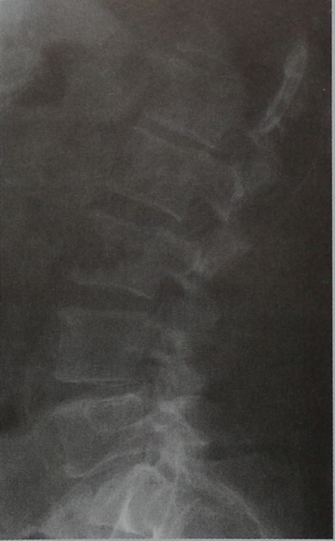

Диагностика

Наиболее прогрессивными методами диагностики рака позвоночника являются КТ (компьютерная томография) и МРТ (магнитно-резонансная томография). С их помощью можно определить точное расположение опухоли, ее форму, размер ее отношение к соседним органам и тканям и наличие метастазов.

Магнитно-резонансная томография представляет собой неинвазивный метод диагностики, который применяется для диагностики рака позвоночника.

МРТ – это сочетание мощных магнитных полей, высокочастотных импульсов и сложной компьютерной системы. Применение этих составляющих помогает получить детальное изображение позвоночника. Снимки, полученные в результате МРТ, тщательно изучаются на компьютере, после чего специалистом выносится то или иное решение о состоянии позвоночника. Подобная информация позволяет ему точно оценить размер опухоли и наличие у нее метастазов, так как данный метод диагностики является наиболее чувствительным в обследовании позвоночника на предмет наличия новообразований.

КТ позвоночника проводится с помощью новейшего оборудования - компьютерного томографа. Это аппарат, состоящий из кольца, оснащенного детекторами, и двигающейся кушетки, на которой лежит пациент. Кушетка входит в кольцо, что позволяет специальной установке выполнять снимки позвоночника больного в разных проекциях и под разными углами.